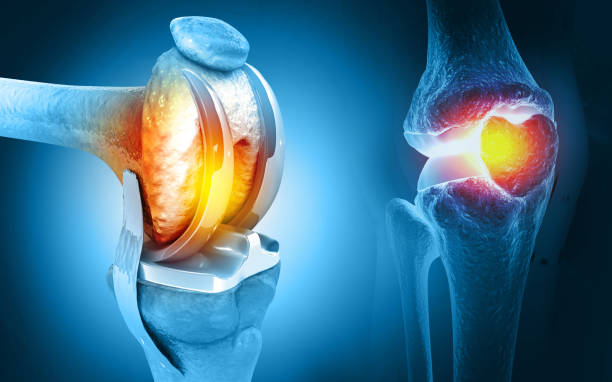

Expertise in joint replacement, arthroscopy, spine care, fractures, trauma, sports injuries, and more — offering personalized treatment to restore mobility and improve quality of life.